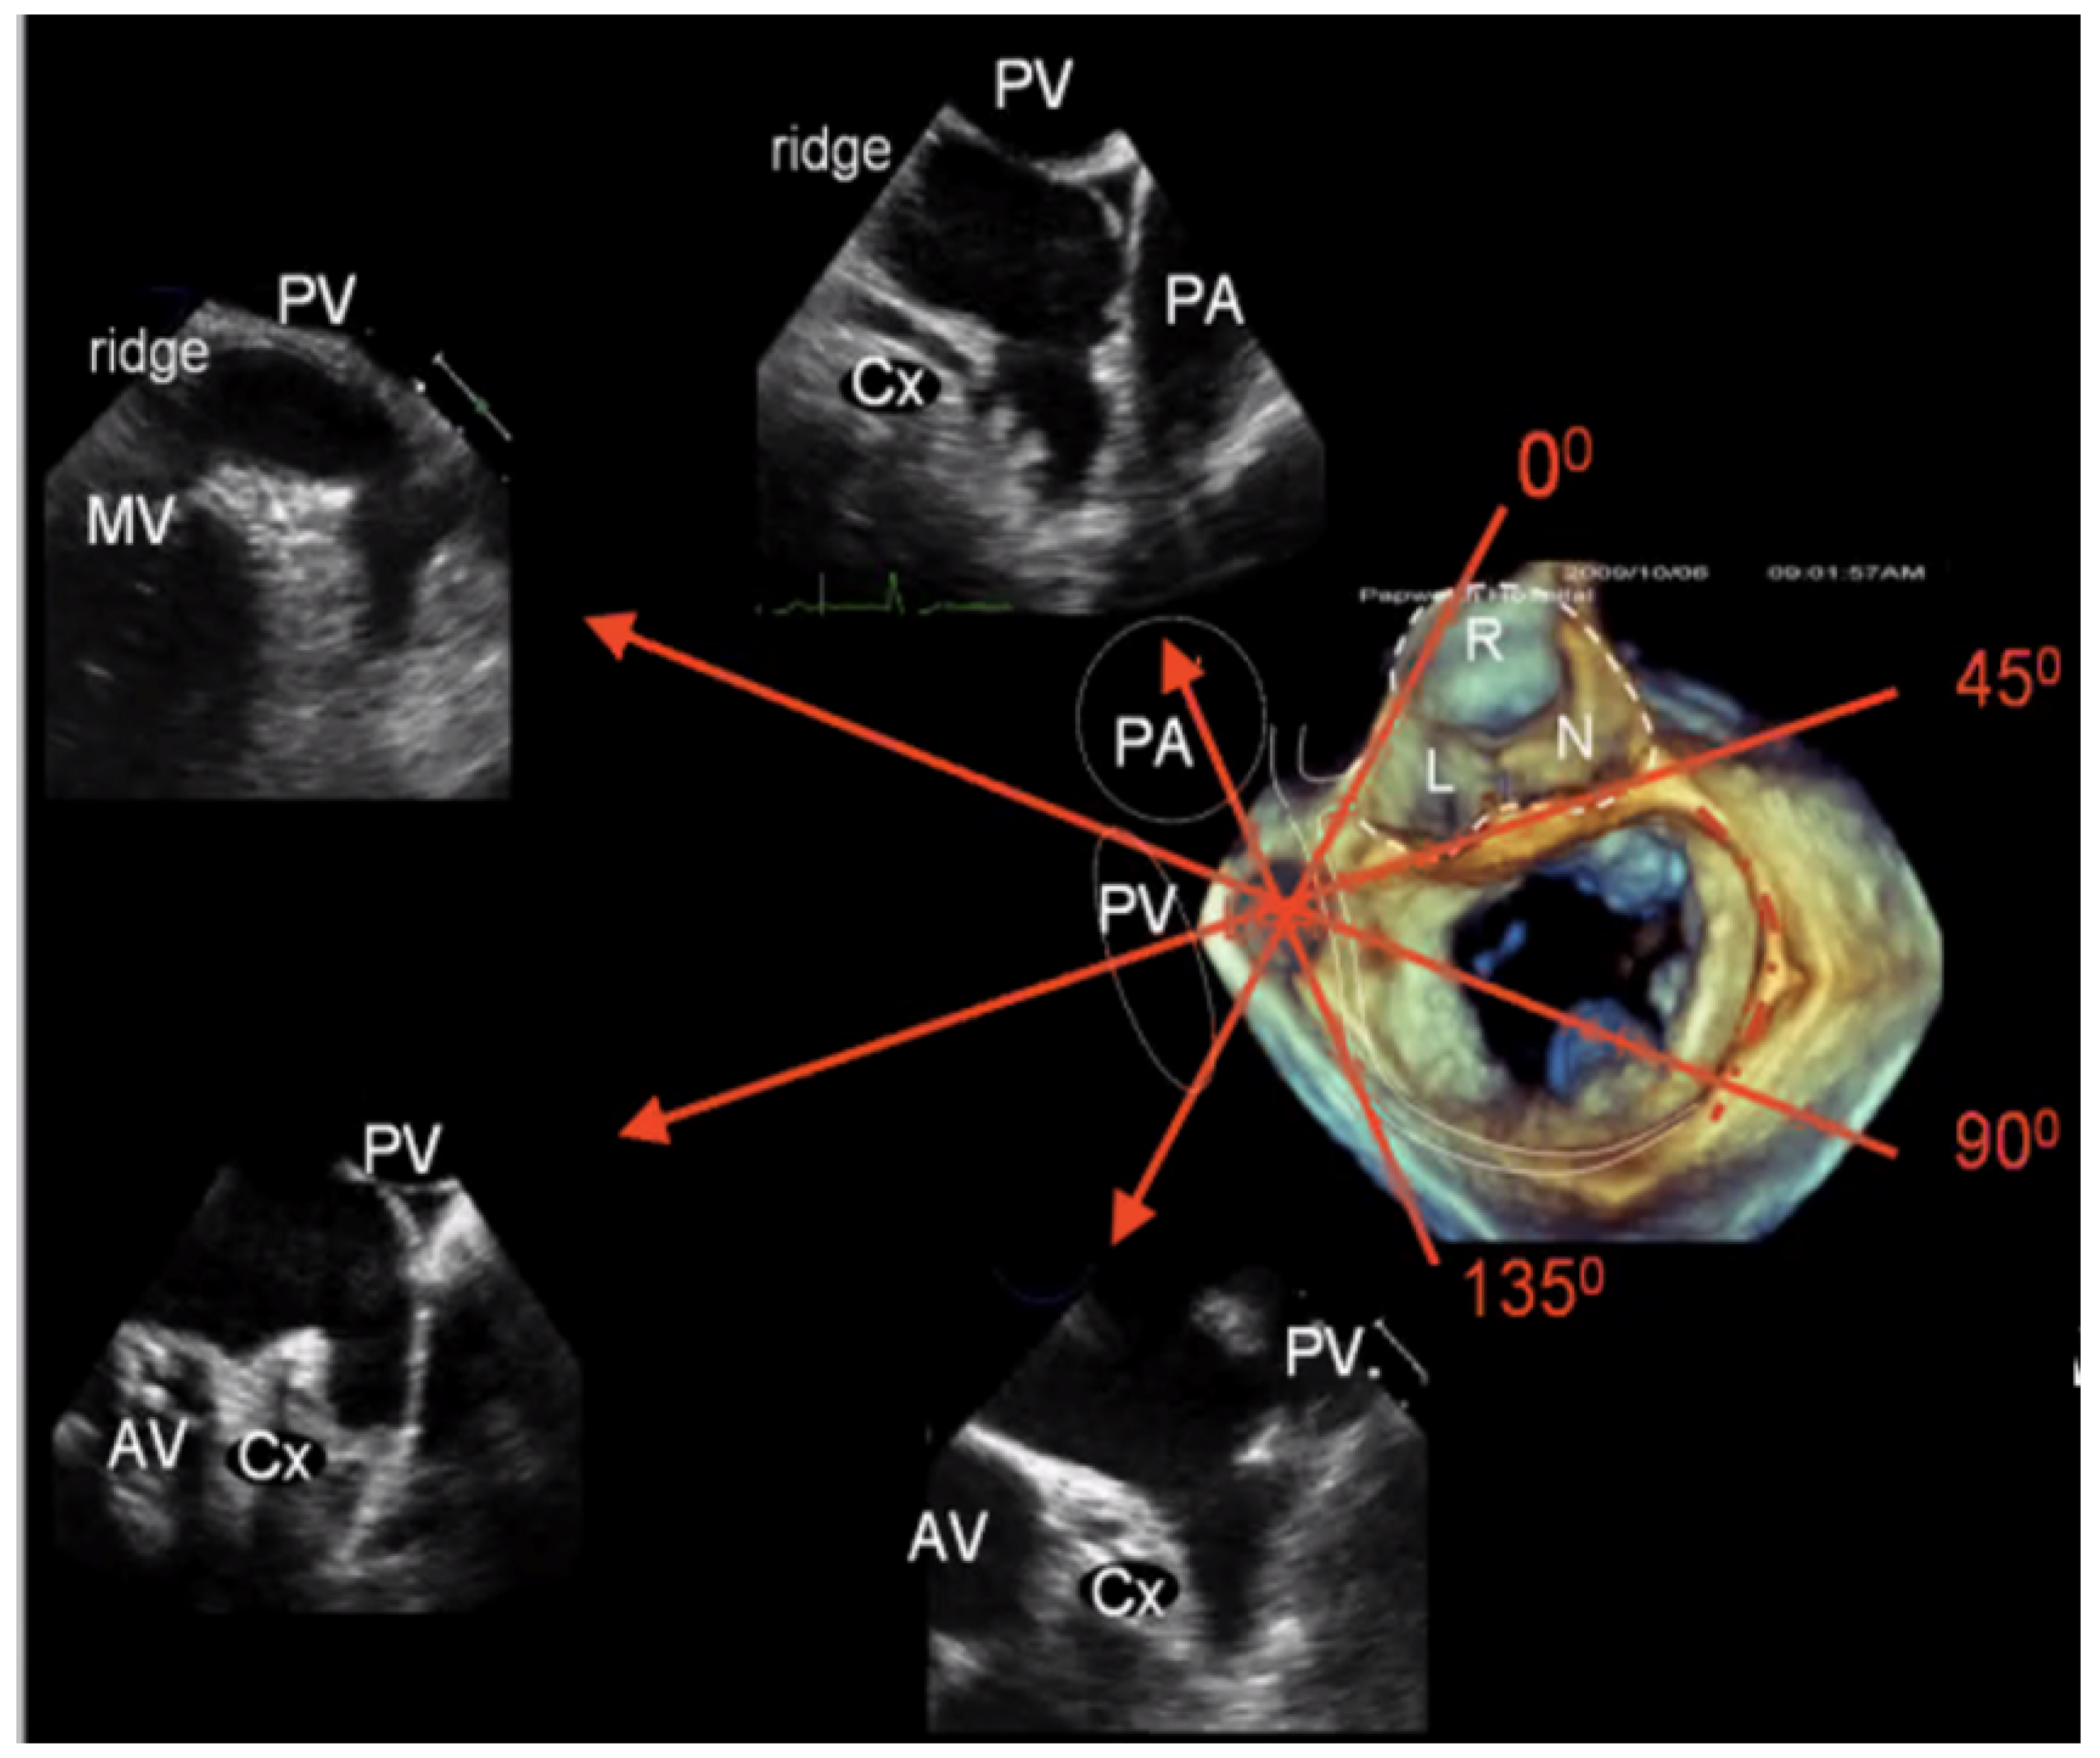

2.2.2. LAA Measurements (Anatomy and Morphology)

2.2.3. Intra-Procedural TOE